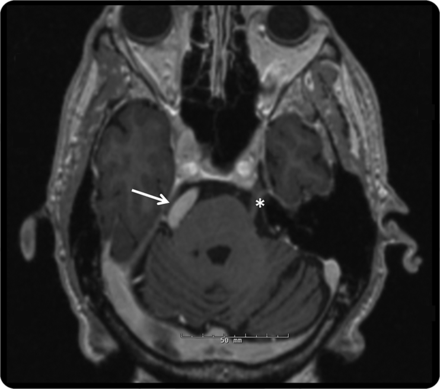

图2

大脑核磁共振,3 d magnetization-prepared快速采集、轴向视图

MRI显示dolichoectatic底动脉扭曲正确的面部神经小脑桥脑角(箭头所指)。作为参考,对侧的面神经显示星号。